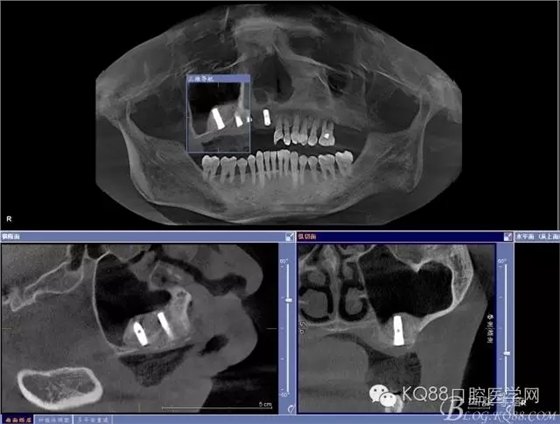

治療計劃:11 12 13及埋伏牙拔除,同期上頜竇外提升手術(shù)及種植修復(fù)

局部浸潤麻醉頰、腭側(cè)手術(shù)區(qū)域,拔除11、12、13.

設(shè)計斜橫切口,從牙槽嵴側(cè)翻開全厚瓣,搔刮牙槽窩內(nèi)肉芽組織,修整牙槽嵴頂。

小球鉆磨除埋伏牙頰側(cè)骨壁,牙挺挺出埋伏牙,清理拔牙窩

金剛砂球鉆制備橢圓形骨窗,遠中邊緣延伸到上頜結(jié)節(jié),取下骨島,骨角和尖銳的邊緣打磨圓鈍,暴露上頜竇黏膜,分離提升上頜竇黏膜。

定位桿定位,擴孔,備洞,bio-oss骨粉和CGF混合后充填竇腔

植入植體,骨島覆蓋上頜骨側(cè)壁骨窗

bio-guide屏障膜覆蓋側(cè)壁骨窗,牙槽嵴頂缺損部位植骨,嚴(yán)密縫合。